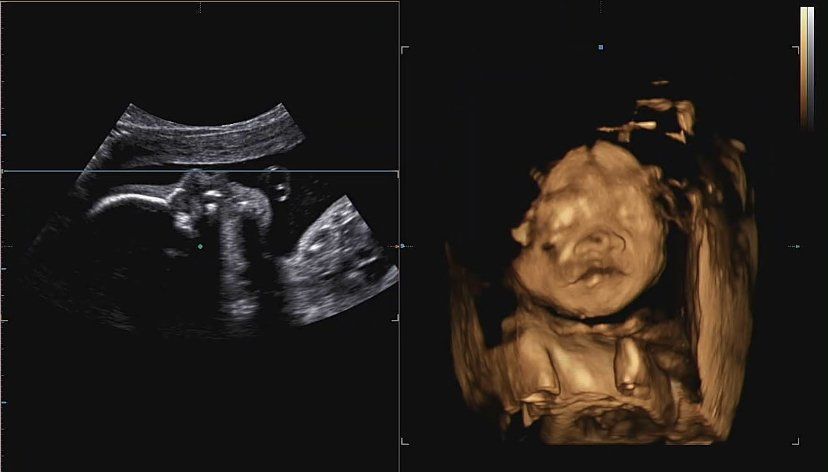

(입체초음파관련 질문)26주 임산부입니다

오늘 입체초음파 다녀왔는데요

당일 산부인과 갔을땐 몰랐는데 집에와서 다시 보니 잘 모르겠어서요 ㅠ

목에 탯줄이 묶여있는건 아니죠? ㅠ

문제있었으면 의사 선생님이 말씀하셨겠지만 마음이 찝찝해서용 ㅠ 고수님 봐주세요

• 올려주신 초음파 컷 하나만으로 확실히 장담드리기는 어렵습니다. 올려주신 초음파 검사 컷들에서는 태아의 목에 탯줄이 묶여있거나 한 것처럼 보이지는 않습니다만 한 컷으로 알 수 있는 정보는 많지 않습니다.